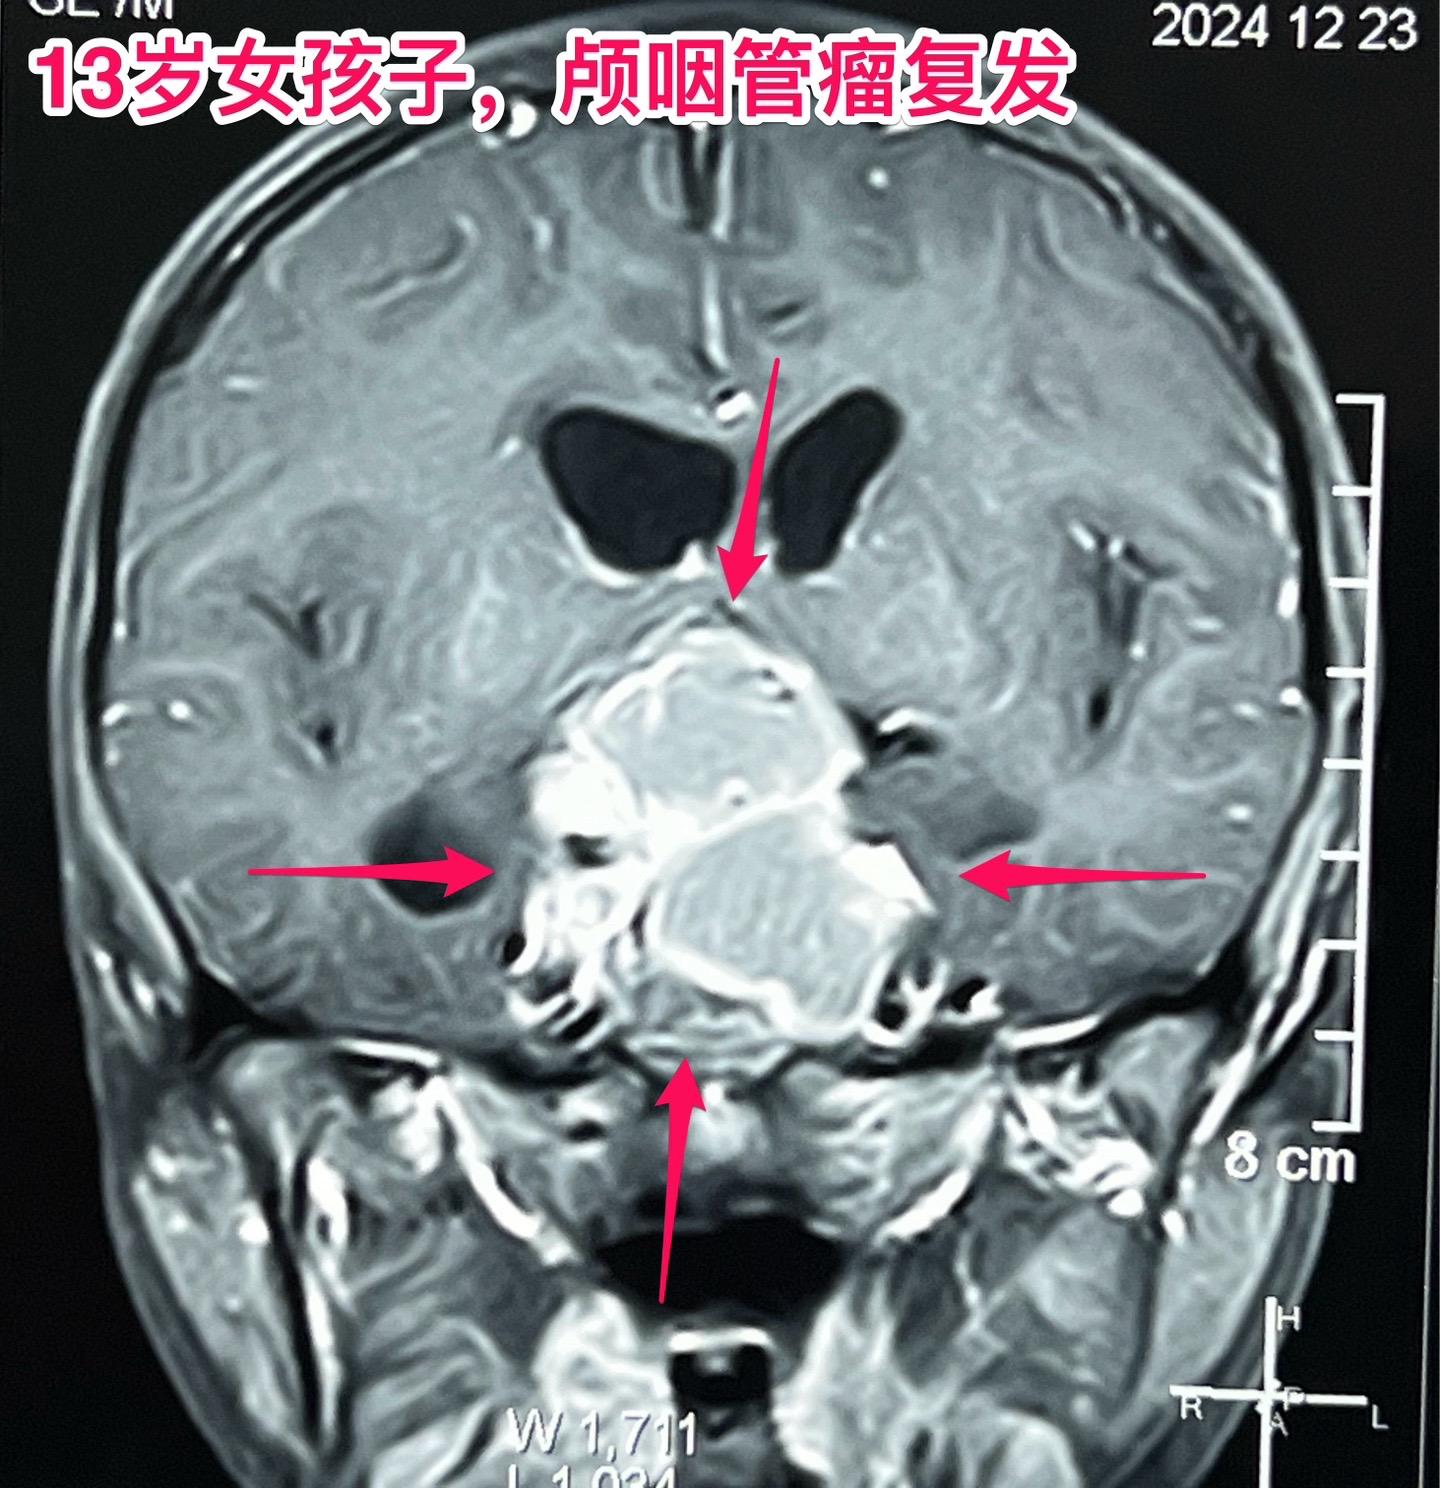

颅咽管瘤两次复发,右眼失明、左眼快失明了。13岁女孩子,因颅咽管瘤之前做过两次开颅手术。肿瘤又复发了,体积很大,垂体窝显著扩大,见图。 12月27日作了手术,将肿瘤完全切除。 这是第三次手术,手术前家长很担心左眼仅有的光感视力会不会变成全盲?会不会出现脑脊液鼻漏? 手术后患者很快就清醒了,左眼视力保住了,也没有脑脊液鼻漏出现。希望肿瘤不再复发。